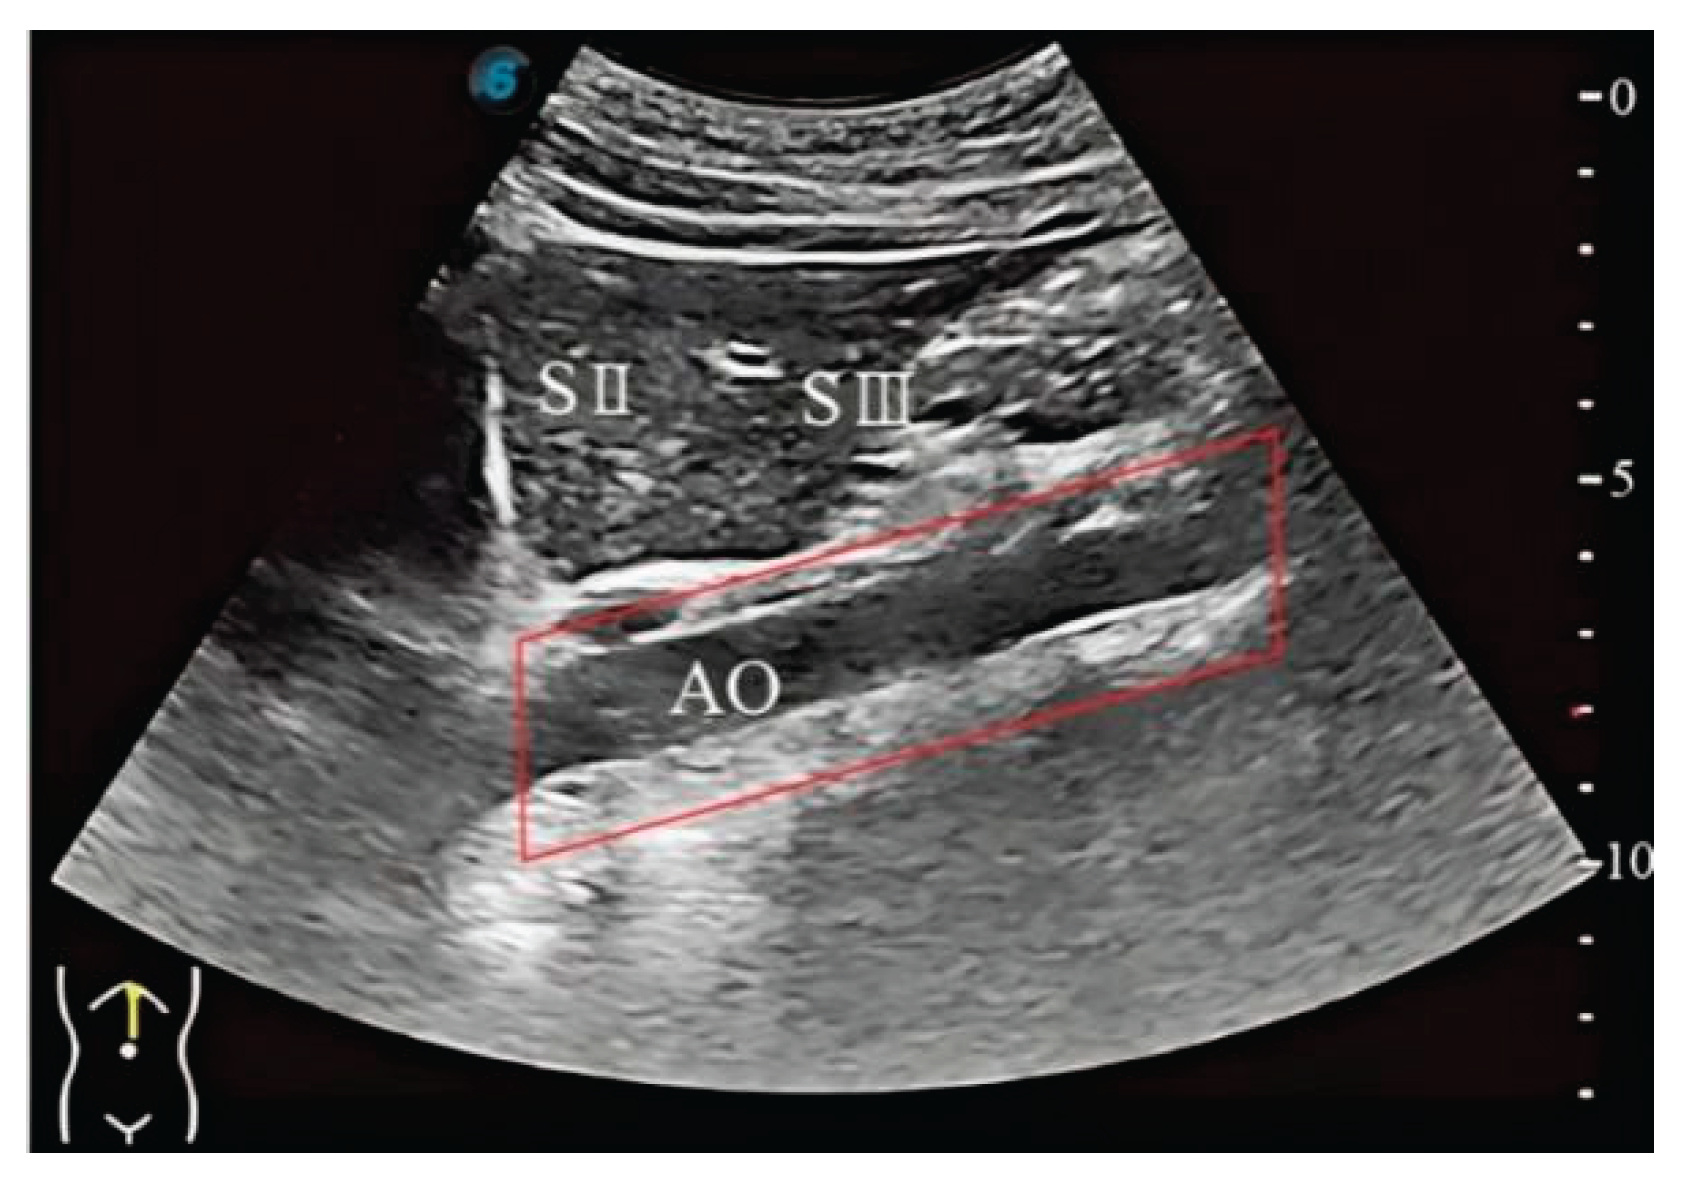

2.2. Liver Standard Plane Localization

3.2. Image Segmentation and Recognition Results